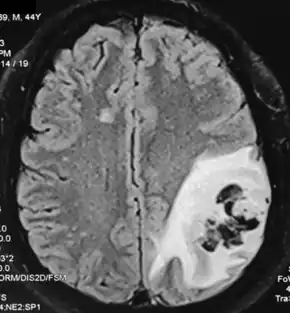

.png.webp)

Although immunoglobulin is frequently used for long periods of time and is generally considered safe, immunoglobulin therapy can have severe adverse effects, both localized and systemic. Subcutaneous administration of immunoglobulin is associated with a lower risk of both systemic and localized risk when compared to intravenous administration (hyaluronidase-assisted subcutaneous administration is associated with a greater frequency of adverse effects than traditional subcutaneous administration but still a lower frequency of adverse effects when compared to intravenous administration). Patients who are receiving immunoglobulin and experience adverse events are sometimes recommended to take acetaminophen and diphenhydramine before their infusions to reduce the rate of adverse effects. Additional premedication may be required in some instances (especially when first getting accustomed to a new dosage), prednisone or another oral steroid.